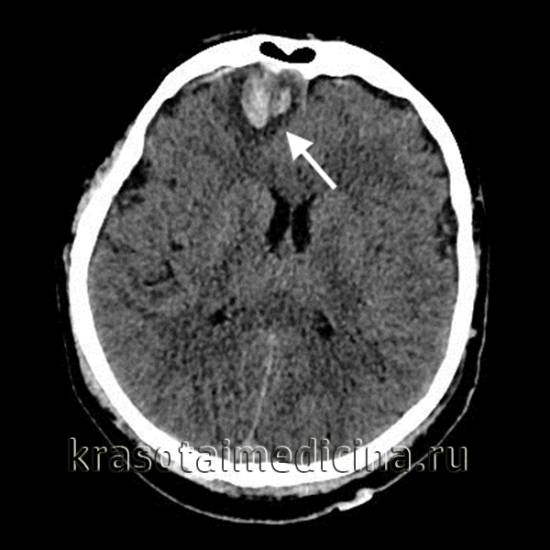

Основным методом диагностики ушибов головного мозга (УГМ) является компьютерная томография (КТ). Томографическая картина зависит от степени тяжести ушиба. При легкой степени очаги с пониженной плотностью выявляются в 40-50% случаев. В зоне ушиба на томограммах наблюдаются отечность и петехиальные кровоизлияния. Отек может охватывать всю долю мозга или даже целое полушарие, что приводит к умеренному сужению ликворных пространств.

На аксиальной КТ головного мозга без контрастного усиления определяется контузионный очаг в правой лобной доле, представленный геморрагическим компонентом, зоной детрита и отека.

Ушиб средней тяжести характеризуется наличием очагов ушиба в виде зон пониженной плотности. При геморрагическом пропитывании очаг может иметь повышенную плотность. При тяжелом ушибе томография показывает очаги как повышенной, так и пониженной плотности. Повышенная плотность указывает на сгустки крови, а пониженная — на участки размозжения и отека. При крайне тяжелых поражениях зона деструкции церебральной ткани проникает в подкорковые структуры.